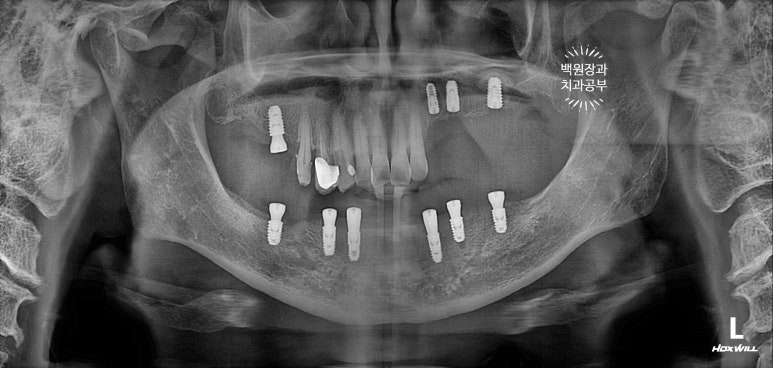

처음 내원하셨을 때 치과용 파노라마 소견입니다.

아래는 이가 하나도 없어 얼마 전 다른 치과에서 제작한 전체틀니를 사용하고 계셨고,

위 어금니는 브릿지로 되어있는데 만성치주염으로 흔들거리는 상황이었습니다.